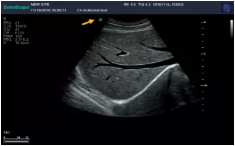

Mark點:每一把探頭都有一個mark點,是用于定位方向, mark點一側(cè)始終對應(yīng)著圖像S點(圖像箭頭標識)一側(cè)。